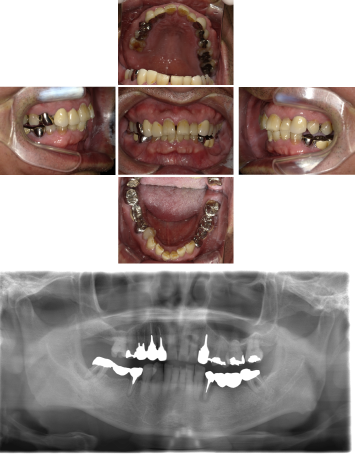

インプラント治療(左上5ソケット・GBR 右上2左上13GBR)

| 年代・性別 | 50代・男性 |

|---|---|

| 主訴 | 入れ歯だと咬めなくてつらい。 |

| 部位 | 上顎②1①2③4⑤Br |

| 治療期間 | 約9ヶ月 |

| 費用 | ¥1,794,100(税込) |

| 副作用・リスク |

|